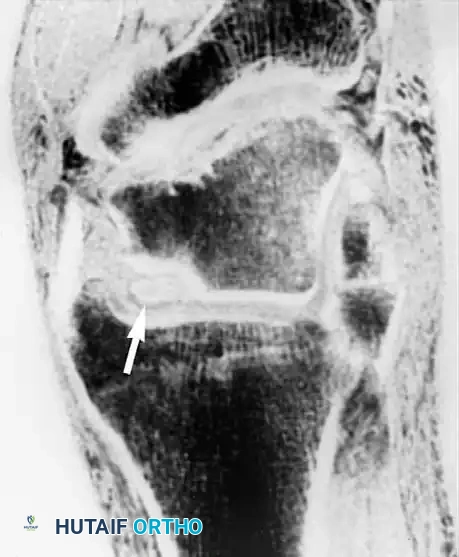

تشخيص إصابات الرباط الصليبي

الرباط الصليبي الأمامي هو المانع الرئيسي لانزلاق عظمة القصبة للأمام. يصور الرنين المغناطيسي بدقة التمزقات الحادة في هذا الرباط، والتي غالبا ما تظهر باتجاه أفقي غير طبيعي للألياف، مع وجود كدمات عظمية مميزة في عظمة الفخذ والقصبة نتيجة اصطدامهما وقت الإصابة.

كما يستخدم الرنين المغناطيسي لتقييم الأربطة الصليبية الخلفية والأربطة الجانبية لضمان سلامتها، وهو أمر حيوي قبل التخطيط لأي جراحة معقدة.